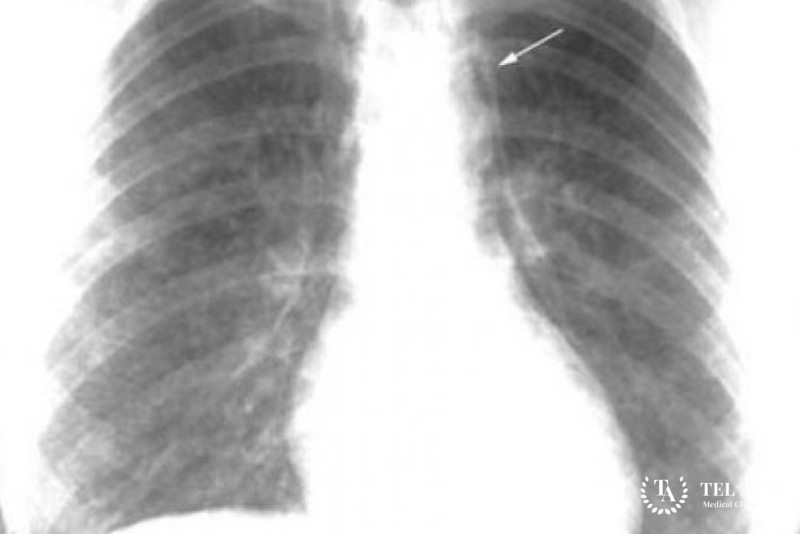

Первичный диагноз специалист ставит на основании осмотра, опроса пациента. Для гистоцитоза Х характерно наличие жесткого, тяжелого дыхания с сухими хрипами в легких. Для выявления врач проводит аускультацию. Подтвердить подозрения на развитие патологического процесса помогают:

- Рентгенография скелетных костей;

- Компьютерная томография;